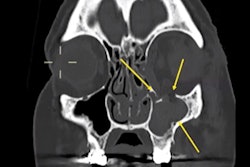

Entry wounds. (A) Axial CT scan shows an entrance wound in the right posterior thoracic wall (white arrow), with adjacent soft-tissue disruption and subcutaneous gas, consistent with a penetrating gunshot injury. (B) Axial CT image depicts the ballistic trajectory with paravertebral left soft-tissue damage (white arrow) and subcutaneous emphysema in the posterior right chest wall. (C) Cross-sectional CT slice demonstrates an entrance wound at the root of the right arm (white arrow), associated with soft-tissue laceration and subcutaneous emphysema. (D) CT image illustrates an entrance wound at the sternal level (white arrow), with anterior chest wall disruption and surrounding soft-tissue alterations, compatible with penetrating trauma. The identification of entrance gunshot wounds showed only moderate inter-reader agreement (Fleiss’ kappa = 0.55). In particular, less forensic-experienced readers demonstrated markedly reduced sensitivity (29.7%), highlighting the diagnostic challenges of detecting these findings on postmortem CT.All figures courtesy of Dr. Maria Grazia Fornasari, Dr. Giuseppe Lo Re, Dr. Roberto Cannella et al and La Radiologia Medica/SIRM.